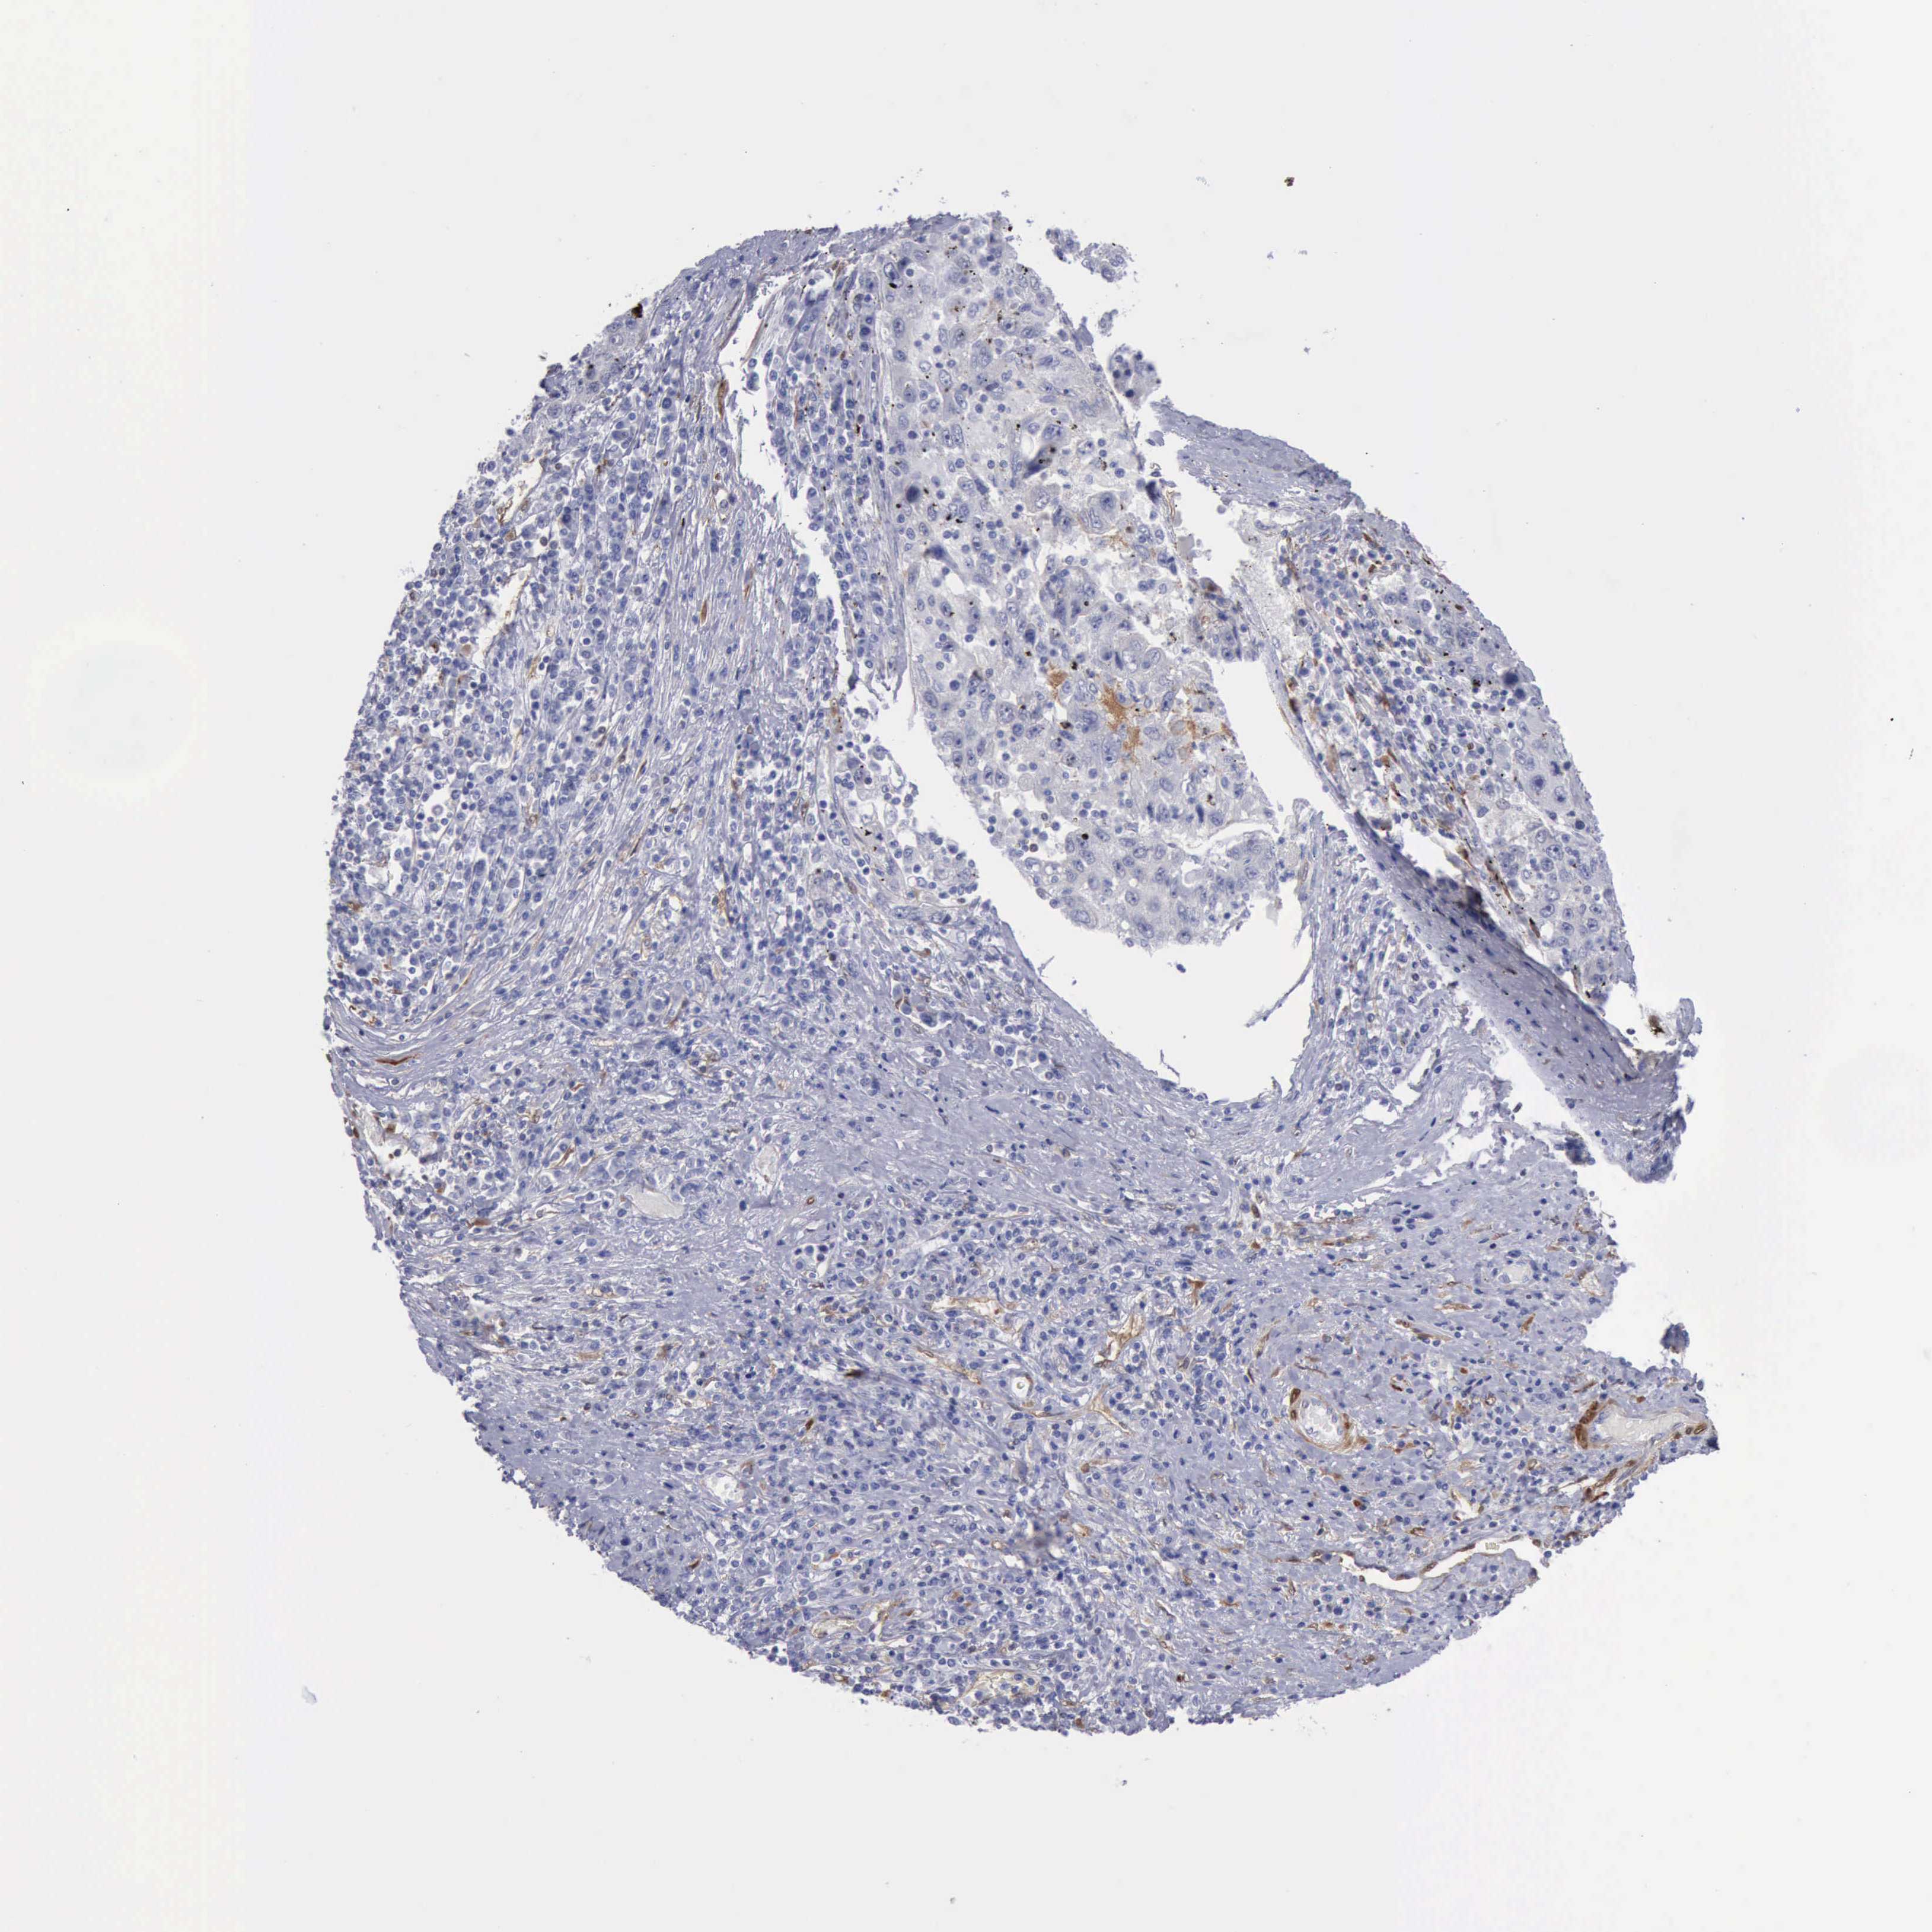

LIVER CANCER - Protein expressioni

A mouse-over function shows sample information and annotation data. Click on an image to view it in a full screen mode. Samples can be filtered based on level of antibody staining by selecting one or several of the following categories: high, medium, low and not detected. The assay and annotation is described here.

Note that samples used for immunohistochemistry by the Human Protein Atlas do not correspond to samples in the TCGA dataset.

Antibody stainingi

Antibody staining in the annotated cell types in the current human tissue is reported as not detected, low, medium, or high, based on conventional immunohistochemistry profiling in selected tissues. This score is based on the combination of the staining intensity and fraction of stained cells.

Each image is clickable and will lead to virtual microscopy that enables deeper exploration of all samples and also displays staining intensity scores, fraction scores and subcellular localization as well as patient and tissue information for each sample.

Antibody HPA001040

Antibody HPA001391

Antibody CAB020817

Staining

High

Medium

Low

Not detected

Intensity

Strong

Moderate

Weak

Negative

Quantity

>75%

75%-25%

<25%

None

Location

Nuclear

Cytoplasmic/membranous

Cytoplasmic/membranous,nuclear

Carcinoma, Hepatocellular, NOS

Cholangiocarcinoma